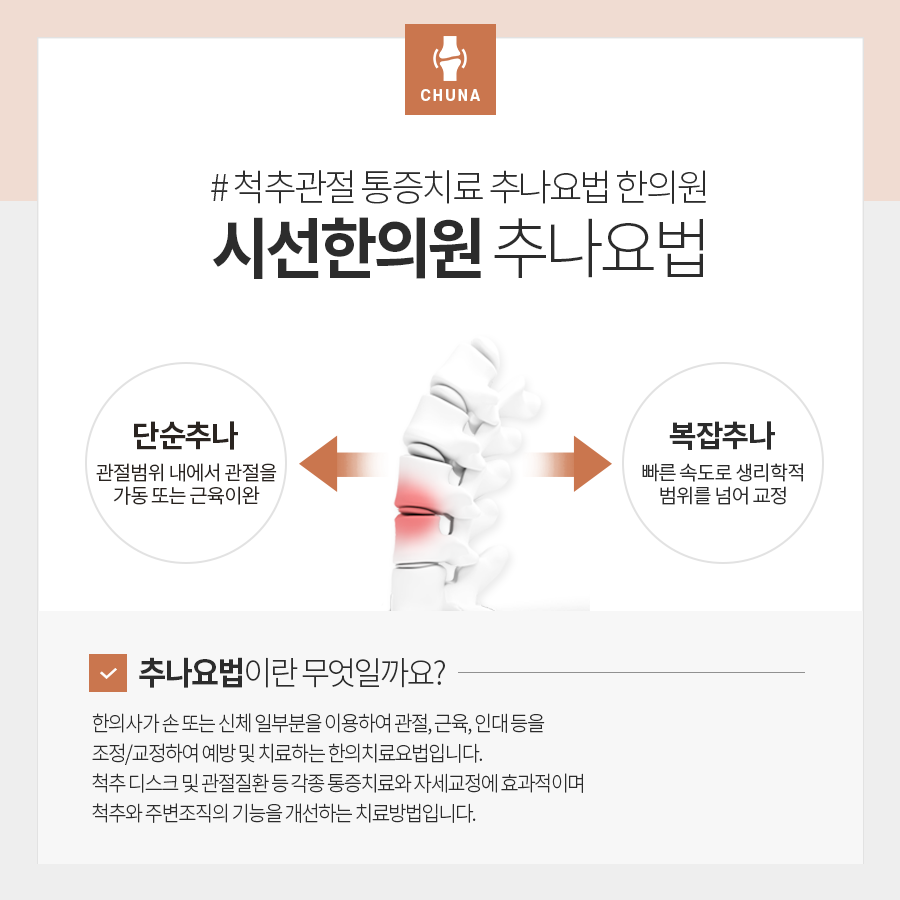

어깨 관절에 이상이 생겨 통증이 생긴다면 진행할 수 있는 치료에는 동래추가요법이 있습니다.시나: 뼈/관절과 함께 근골격을 압박하는 방법으로 이상이 발생한 곳을 교정하거나 이완시켜 회복을 돕는 치료법입니다.

동래추나요법은 시행방법 및 예비목적에 따라 뼈의 불균형을 직접 바로잡아 교정하는 정골추명과 근막의 이완을 도와 운동성 회복을 돕는 경추명으로 구분할 수 있습니다.